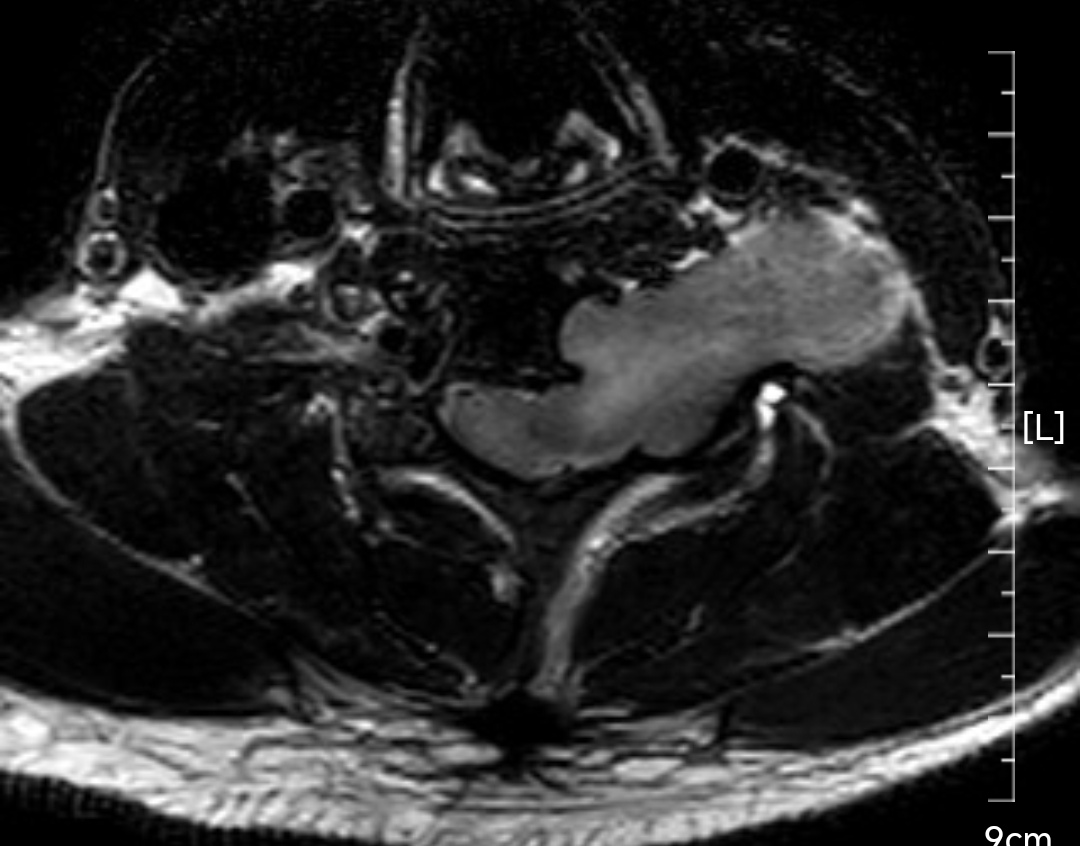

颈椎哑铃型神经纤维瘤,椎间孔汇合,安全又便于操作~